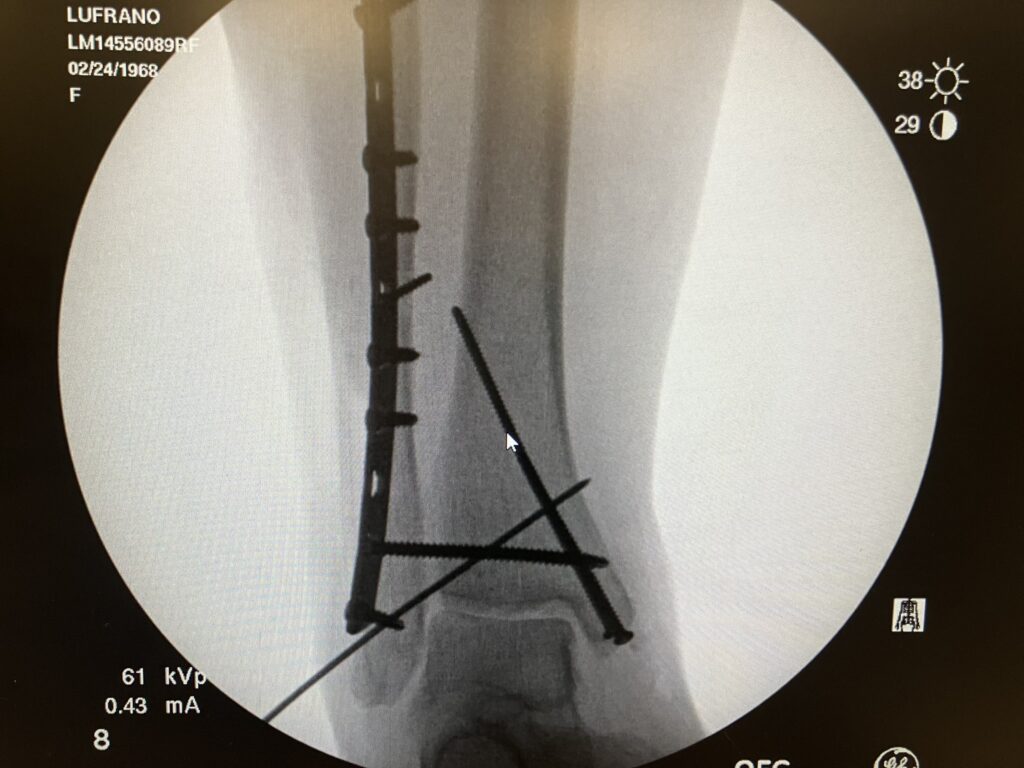

Sorry to report that I spent a few days in the hospital. I was carrying foster puppy KALI outside to potty Sunday afternoon, and I slipped on some ice and fell. Broke my ankle, dislocated my ankle, and broke both bones in my shin. Sunday night they sedated me to yank everything back into alignment. All hail good meds. Apparently, I narrated my hallucinations. I had surgery Monday morning, and they pinned, screwed, and plated everything back together. Sounds like 8-10 weeks of NON-weight-bearing life for me. Gah! They gave me a nerve block before surgery, but that’s starting to wear off now now that I’m home, etc.

Before and after surgery x-rays. They realigned things Sunday evening in the ER. Gave the team a little scare when I stopped breathing for a bit, but I guess they hollered and shook me, and I started breathing again. Instead of your regular old orthopedic surgeon, they have a team of trauma / ortho surgeons who specialize in piecing people back together. I’m so grateful to receive access to their skill and expertise.